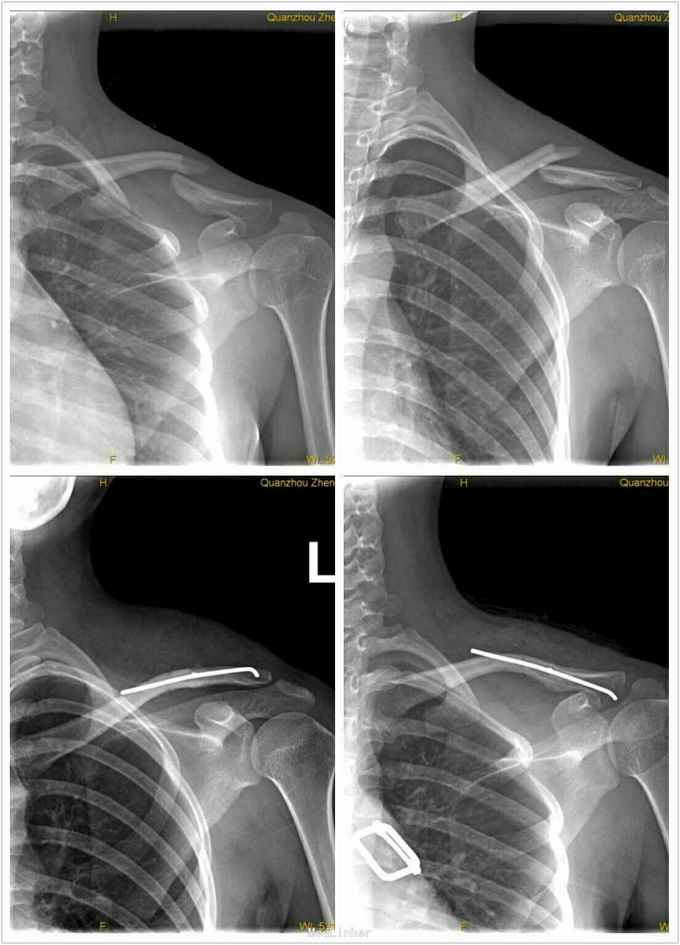

锁骨骨折闭合复位弹性钛针固定一例

锁骨骨折x光图片

锁骨骨折错位图片

锁骨骨折图片实拍